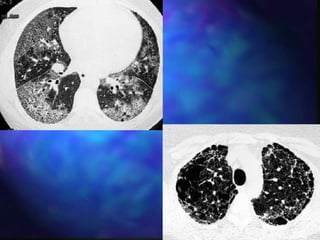

Diagnosis

s   Diagnosis is often suggested by history, chest

radiograph and high resolution CT scan of the

lungs.

HRCT – subpleural nodules

HRCT in Acute HP